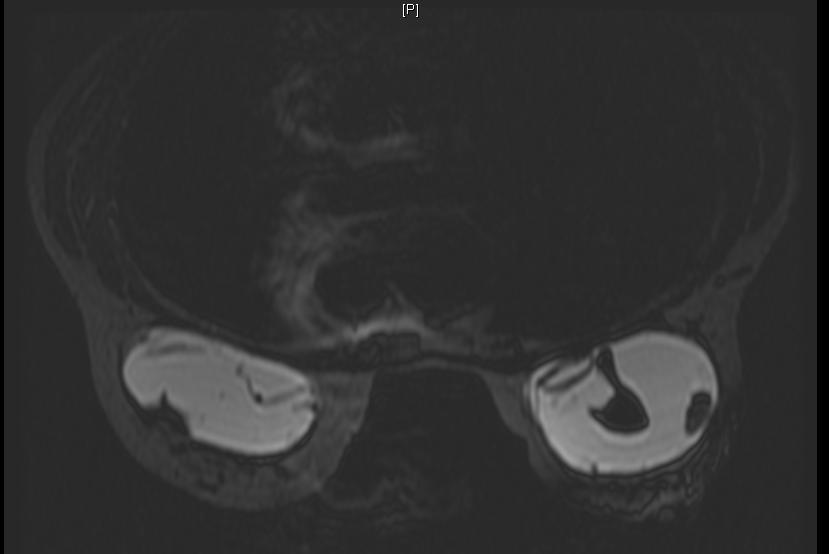

Breast implant ruptured